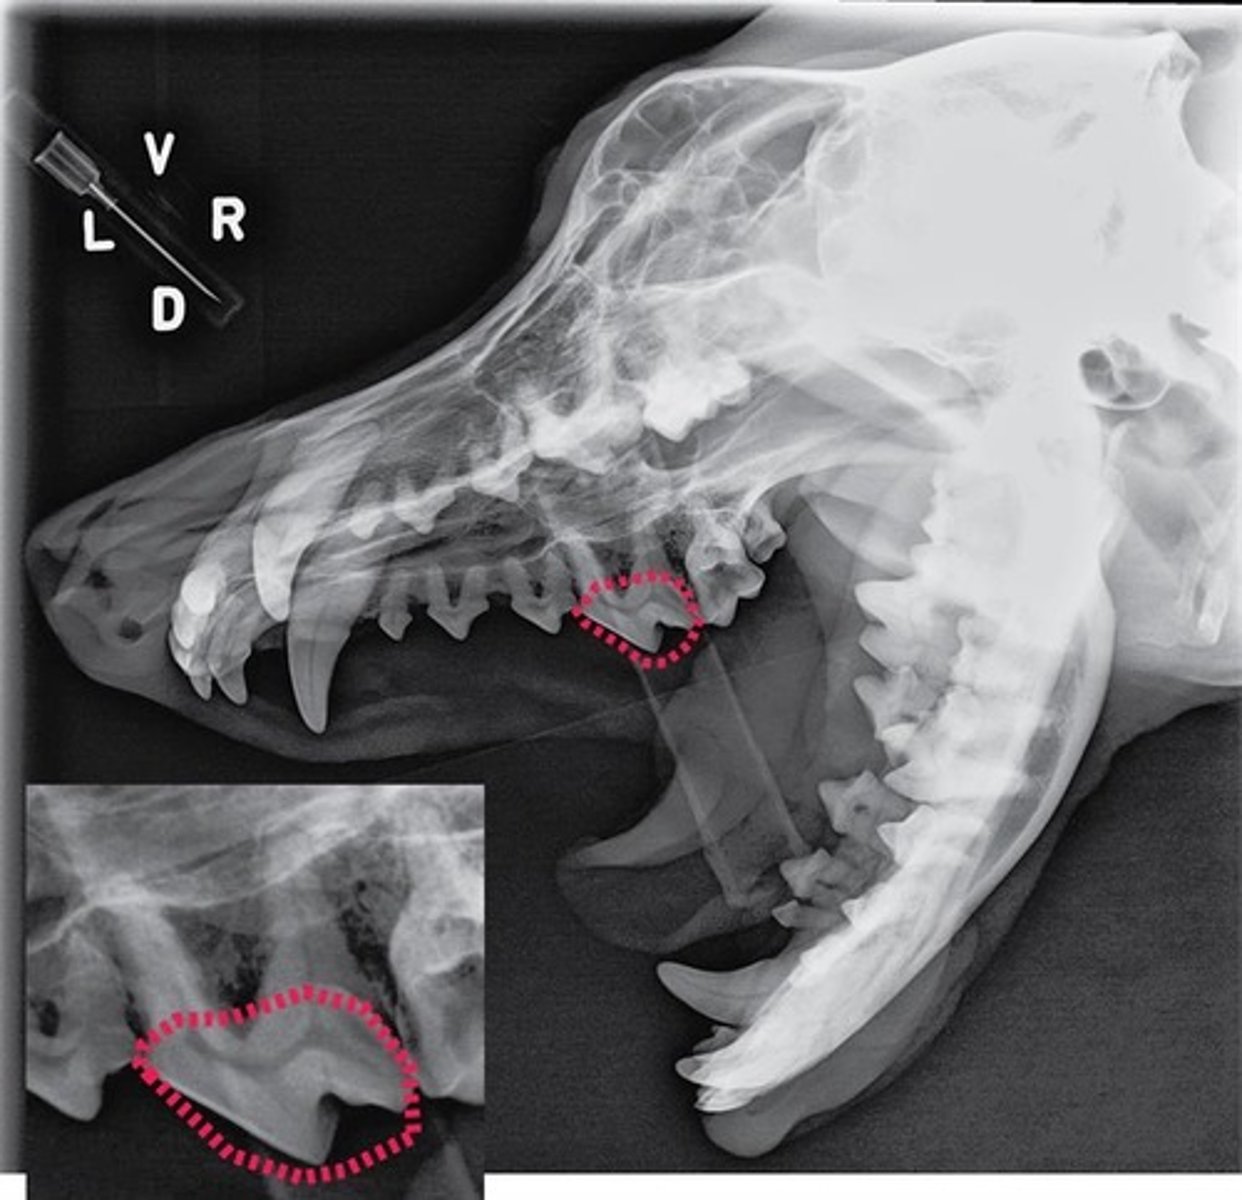

Using the Triadan system, enter the three-digit number that corresponds to the tooth pointed at by the arrow.

309

Using the Triadan system, enter the three-digit number that corresponds to the tooth pointed at by the arrow.

404

Using the Triadan system, enter the three-digit number that corresponds to the tooth highlighted.

704

Canine is #04 and in quadrant 3, so add 4 to the quadrant to get 7 and that equals 704

Triadan number for lower left deciduous canine.